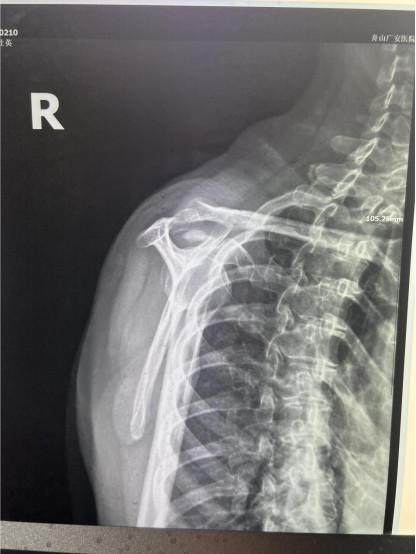

賀大媽慕名來(lái)廣安醫(yī)院找羅軍主任就診,面對(duì)羅醫(yī)生,賀大媽哭訴:“羅醫(yī)生,我真想剁下自己的這只胳膊。”羅軍主任根據(jù)患者的癥狀拍片,診斷為岡上肌鈣化性肌腱炎,隨后,羅醫(yī)生為李大媽進(jìn)行了肩關(guān)節(jié)鏡微創(chuàng)手術(shù),竟從她的右肩“擠”出“牙膏”。

鈣化性肌腱炎是一種自限性疾病,就是疾病發(fā)生發(fā)展到一定程度后,經(jīng)長(zhǎng)期機(jī)體調(diào)節(jié)能夠控制病情發(fā)展并逐漸恢復(fù)痊愈。它分為四個(gè)階段:鈣化前期、鈣化形成期、鈣化吸收期、鈣化后期,往往在“鈣鹽斑塊”吸收時(shí),疼痛最劇烈,賀大媽就正處于“吸收期”。

是不是只要病人撐得住,讓鈣鹽吸收就沒(méi)事了?羅軍主任表示,經(jīng)保守治療無(wú)法緩解或病程長(zhǎng)的患者,應(yīng)盡早采取手術(shù)治療。而且,部分患者鈣鹽無(wú)法完全吸收,拖下去只會(huì)使病情惡化,造成肩膀肩袖肌腱的損傷。